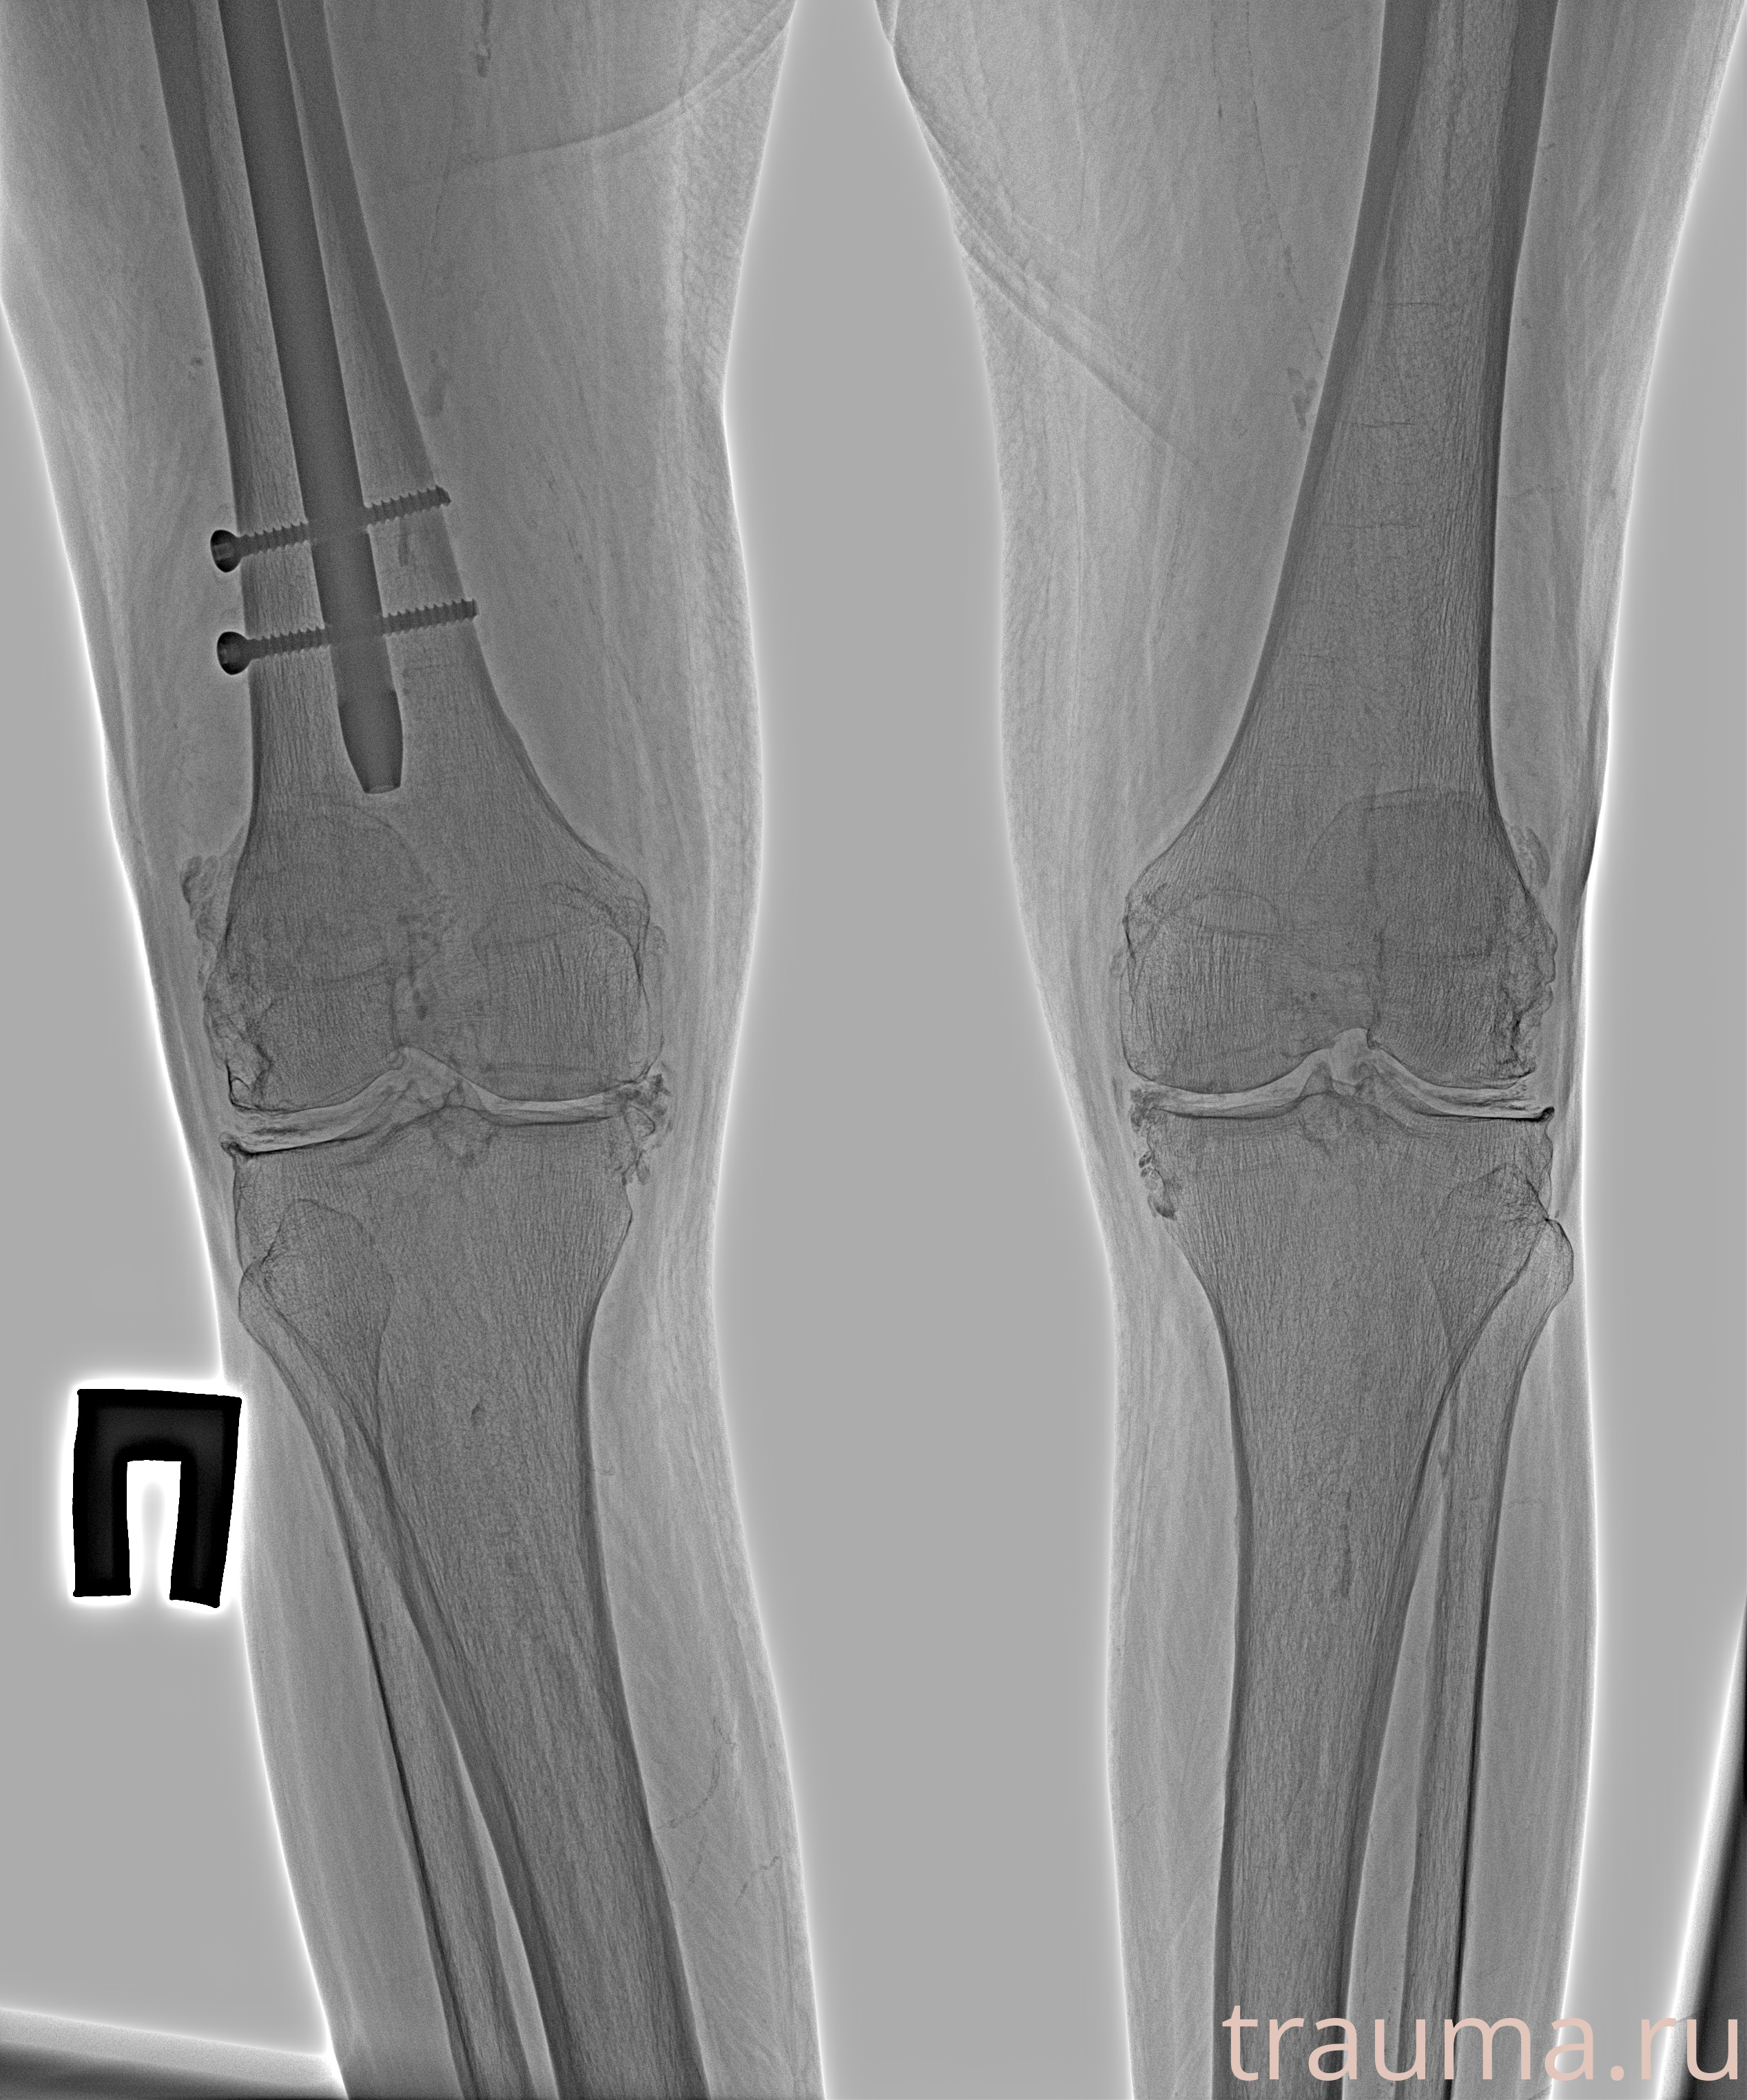

Рентгенограммы

Рентген на дому: по вашему адресу приезжает врач-рентгенолог, травматолог-ортопед с мобильным рентгеновским аппаратом, проводит диагностику травмы или заболевания, делает необходимые рентгенограммы, дает рекомендации по дальнейшему лечению. Получить качественные снимки в домашних условиях возможно благодаря уникальной методике, разработанной МосРентген Центром для института  Склифосовского